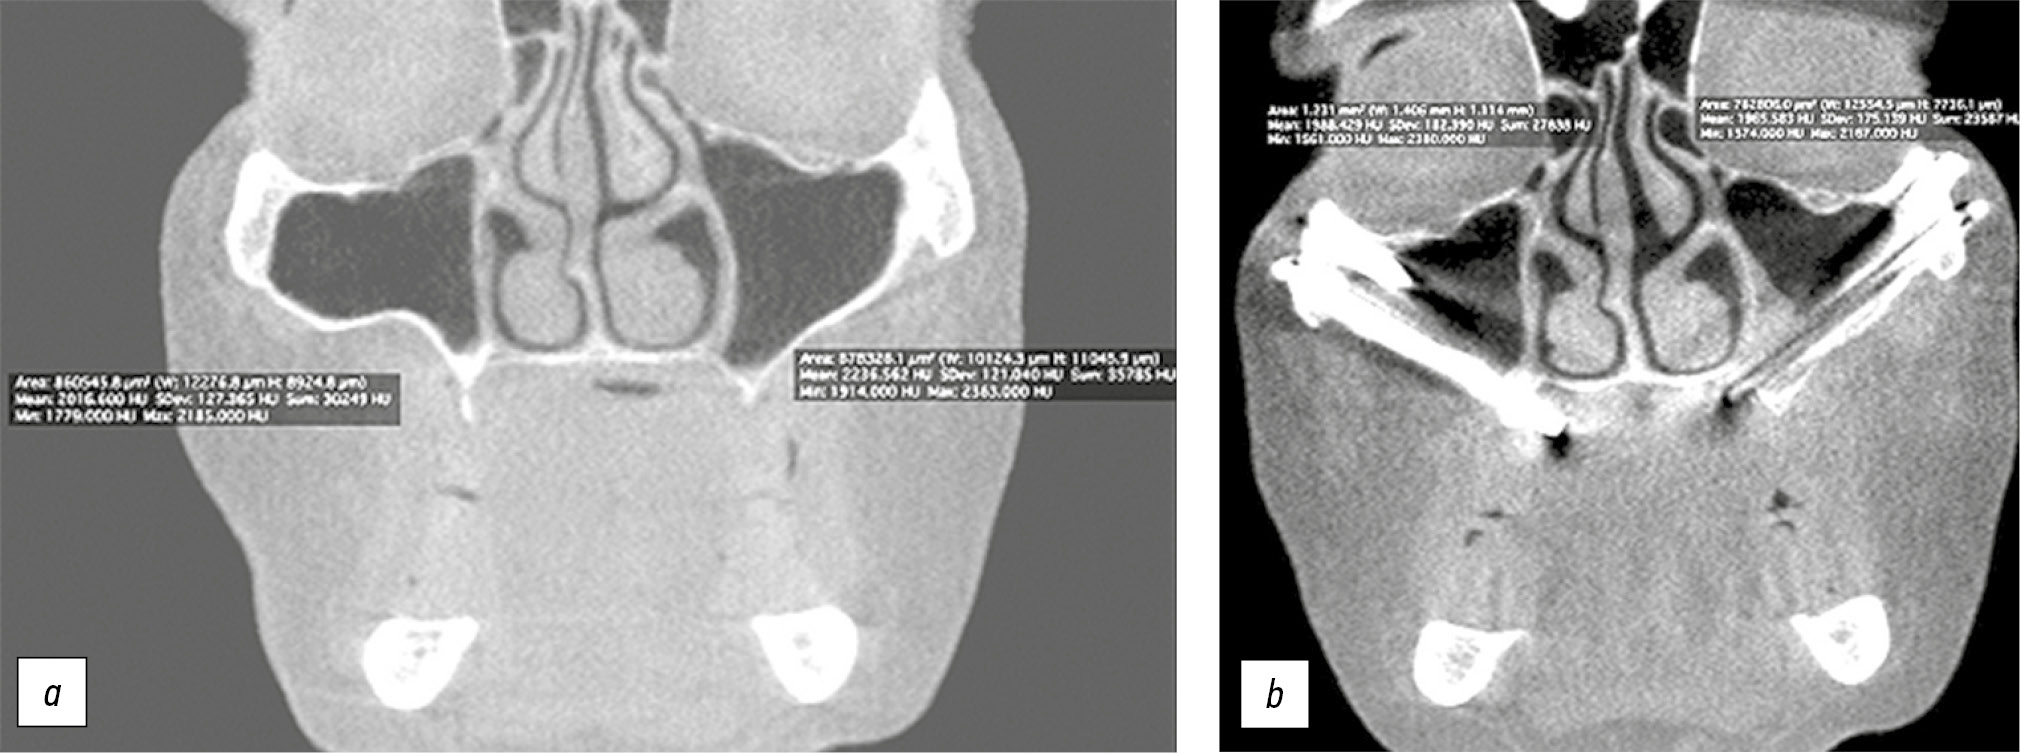

Рис. 4. Предоперационное компьютерное планирование позиции и размеров скуловых имплантатов: a — прямая проекция; b — аксиальная проекция.

Fig. 4. Preoperative computer planning of zygomatic implant position and size: a — anterior projection; b — axial projection.

При предоперационном планировании оперативного вмешательства были определены оптимальные положения (в том числе углы наклонов) и размеры скуловых имплантатов: мезиальные — длина 52,5 мм, диаметр 4,1 мм; дистальные — длина 45,0 мм, диаметр 4,1 мм. Также были определены необходимые параметры дентальных имплантатов: мезиальные — стандартные, длина 11,5 мм, диаметр 4,0 мм; дистальные — угловые (24°), длина 13,0 мм, диаметр 4,0 мм. Положения скуловых имплантатов соответствовали 2-му типу по классификации ZAGA, предложенной C. Aparicio [15].

Предварительно в компьютерной программе Blue Sky Plan (Blue Sky Bio, LLC, США) осуществляли виртуальную моделировку по данным компьютерной томографии, проведённой по стандартному протоколу лучевого обследования и визуализации. При этом применяли принцип «обратного планирования», то есть скуловые имплантаты позиционировали в области верхней челюсти, учитывая требования планирующейся ортопедической конструкции с опорой на них. Данная процедура позволяет обеспечить точную и последовательную установку скуловых имплантатов, выбор их размеров и соблюдение параметров ортопедической конструкции (рис. 4).